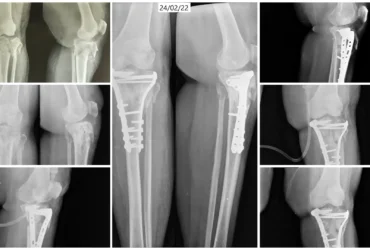

Right PCL Avulsion Fracture Treated with PCL Avulsion Fixation | Balanku Hospital

Huligeppa with right PCL avulsion fracture and knee instability underwent successful PCL avulsion fixation at Balanku Hospital and achieved complete recovery of knee range of...

We Provide Orthopedic Service by Experience Doctors

We has a dedicated multidisciplinary team that cares for and surgically repairs acute fractures for patients of all ages. We offer expertise in fractures of the hip, arm, leg, hand, foot and ankle.